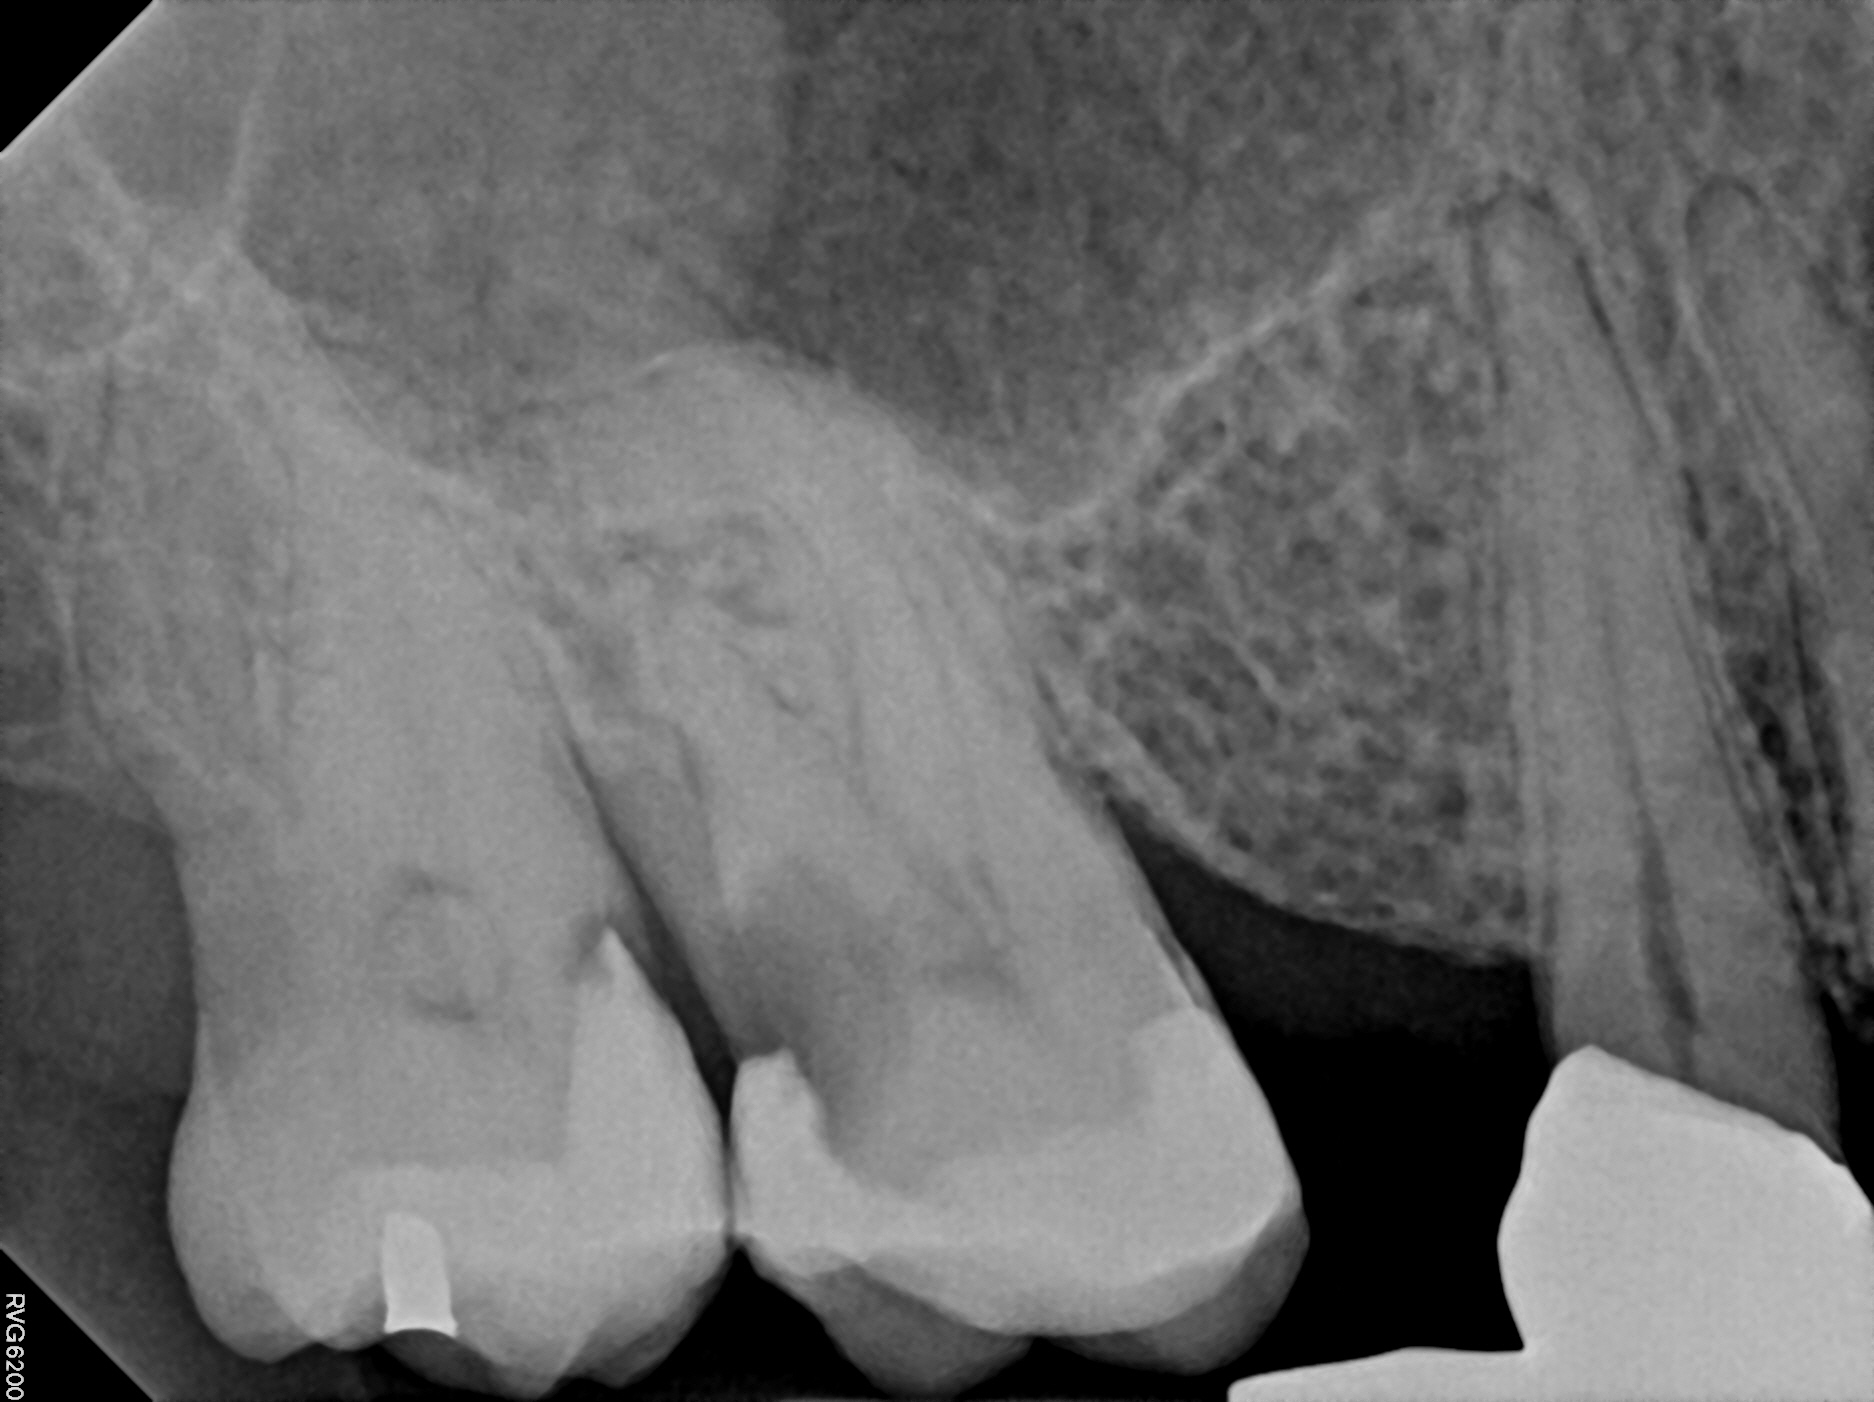

Case 4

A very large infection with a lower molar. The infection extended far from the offending molar and contacts the adjacent teeth. This can lead to the other teeth becoming infected as well, but luckily for this patient, the adjacent teeth were just fine when we started treatment. The right image (one year later) shows the dramatic healing of bone re-growing into the hold in his jaw created by the previous infection. The adjacent teeth remained in good health.